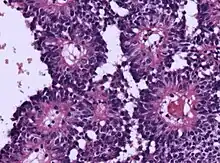

Micrograph of an astroblastoma showing the characteristic nuclear pervivascular pseudorosette. H&E stain.